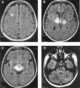

Leukoencephalopathy - thalamus and brainstem anomalies - high lactate

Brainstem anomaly

High lactate

Thalamus anomaly